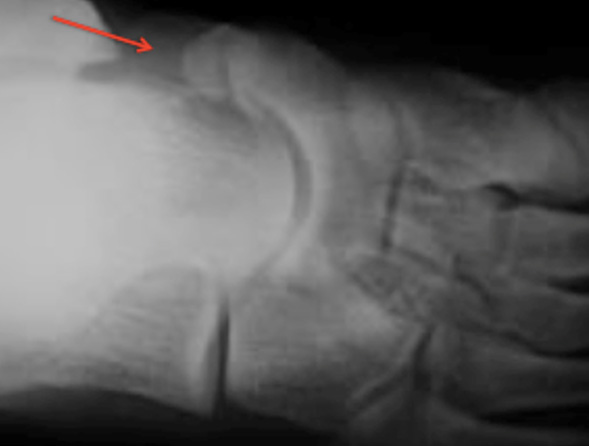

Geralmente o estudo é complementado com exames auxiliares de diagnóstico, como a radiografia dos pés em carga, onde podemos identificar o osso acessório. A ressonância magnética é de extrema importância nesta patologia para avaliar o estado tendinoso (inflamação ou rotura parcial do tendão tibial posterior) e para avaliar a presença de edema ósseo na região da sincondrose.